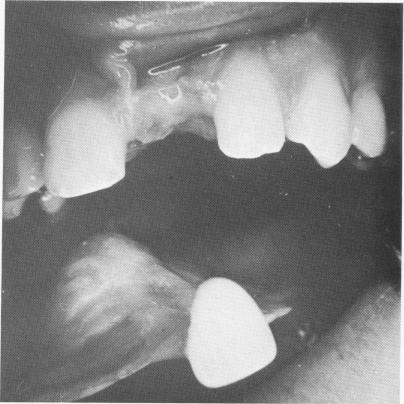

Fig. 11-27. A missing left maxillary central incisor originally restored with a removable prosthesis.

In this case a restoration for a left central maxillary incisor was planned (Fig. 11-27) . The fibro-